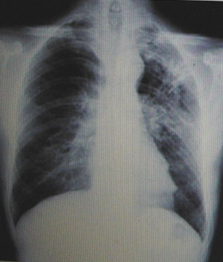

男性,23歲,午后低熱2周。

A.左上肺炎

B.左上支氣管擴(kuò)張

C.左上浸潤(rùn)型肺結(jié)核

D.正常胸片

『正確答案』C